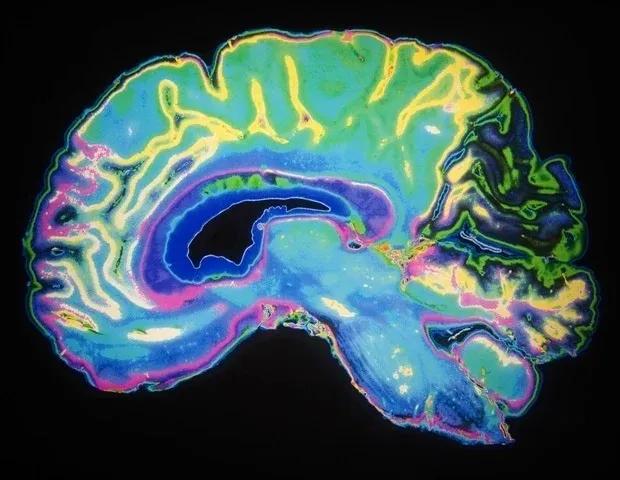

A completed run, the early morning hit of caffeine, the smell of cookies in the oven - these rewarding moments are all due to a hit of the neurotransmitter dopamine, released by neurons in a neural network in our brain, called the "dopaminergic reward pathway". Apart from mediating the feeling of "reward", dopaminergic neurons also play a crucial role in fine motor control, which is lost in diseases such as Parkinson's disease. Despite dopamine's importance, key features of the system are not yet understood, and no cure for Parkinson's disease exists. In their new study, the group of Jurgen Knoblich at IMBA developed an organoid model of the dopaminergic system, which not only recapitulates the system's morphology and nerve projections, but also its functionality.

The team first developed organoid models of the so-called ventral midbrain, striatum and cortex - the regions linked by neurons in the dopaminergic system - and then developed a method for fusing these organoids together. As happens in the human brain, the dopaminergic neurons of the midbrain organoid send out projections to the striatum and the cortex organoids. "Somewhat surprisingly, we observed a high level of dopaminergic innervation, as well as synapses forming between dopaminergic neurons and neurons in striatum and cortex", Reumann recalls.